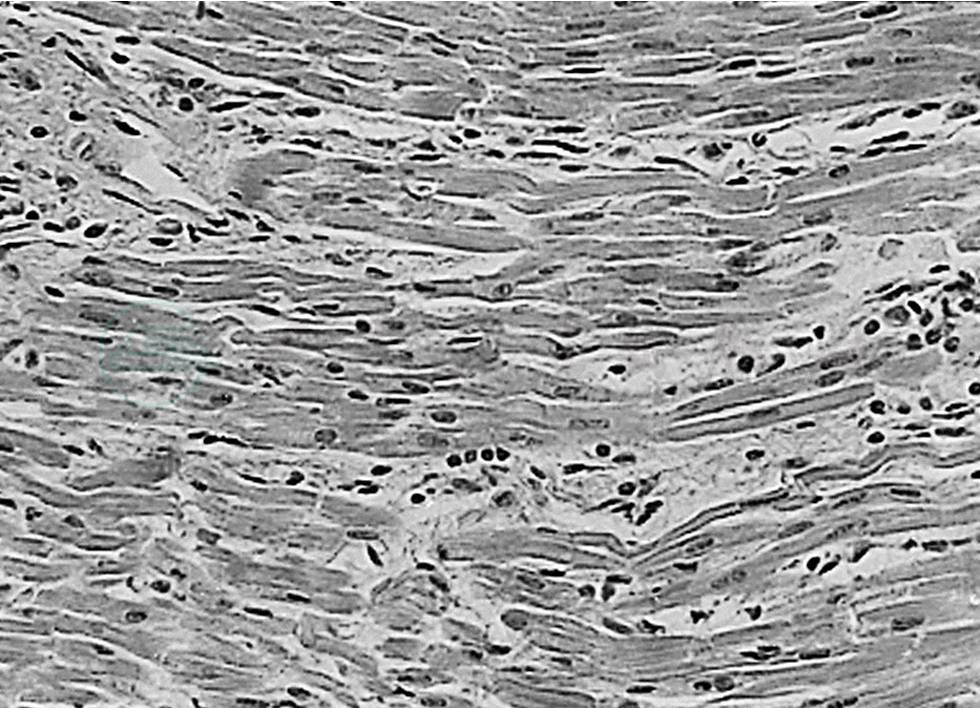

Ⅱ期:约2~4周,其特点为:①小血管的发炎减轻;②以中等动脉的炎变为主,多见冠状动脉全血管炎,形成动脉瘤及血栓;③大动脉全血管性炎变少见;④单核细胞浸润或坏死性变化较显著(图1、图2)。

图2弥漫性间质性心肌炎

血管炎变之外,病理还涉及多种脏器,尤以弥漫性间质性心肌炎、心包炎及心内膜炎最为显著,并波及传导系统,可在Ⅰ期引起死亡。冠状动脉瘤破裂及血栓是Ⅱ、Ⅲ期死亡的重要原因。到了第Ⅲ、Ⅳ期则常见缺血性心脏病变,心肌梗死可致死亡。